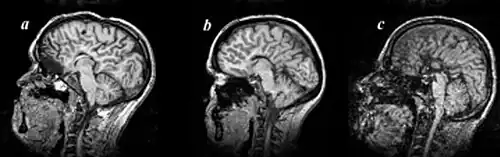

MRI images of three patients in the sagittal plane. A and B: Complete agenesis of the corpus callosum. C: Complete agenesis of both the corpus callosum and the anterior commissure.